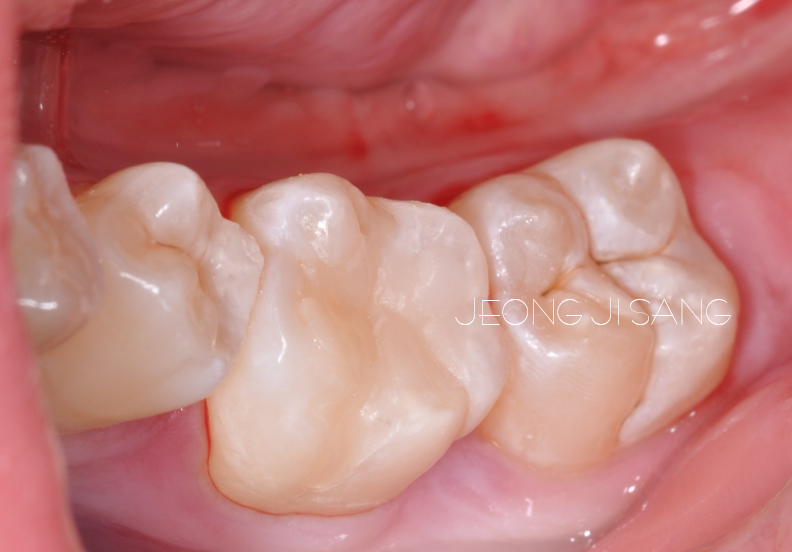

옆에서 보면 이렇습니다.

지금까지도 잘 사용하고 계시는데요.

예전에 치료받은 ‘지아이’같이 쉽게 파절되거나 마모되지는 않을 것입니다.

앞으로도 오래 오래 잘 사용하시기를 바라겠습니다.